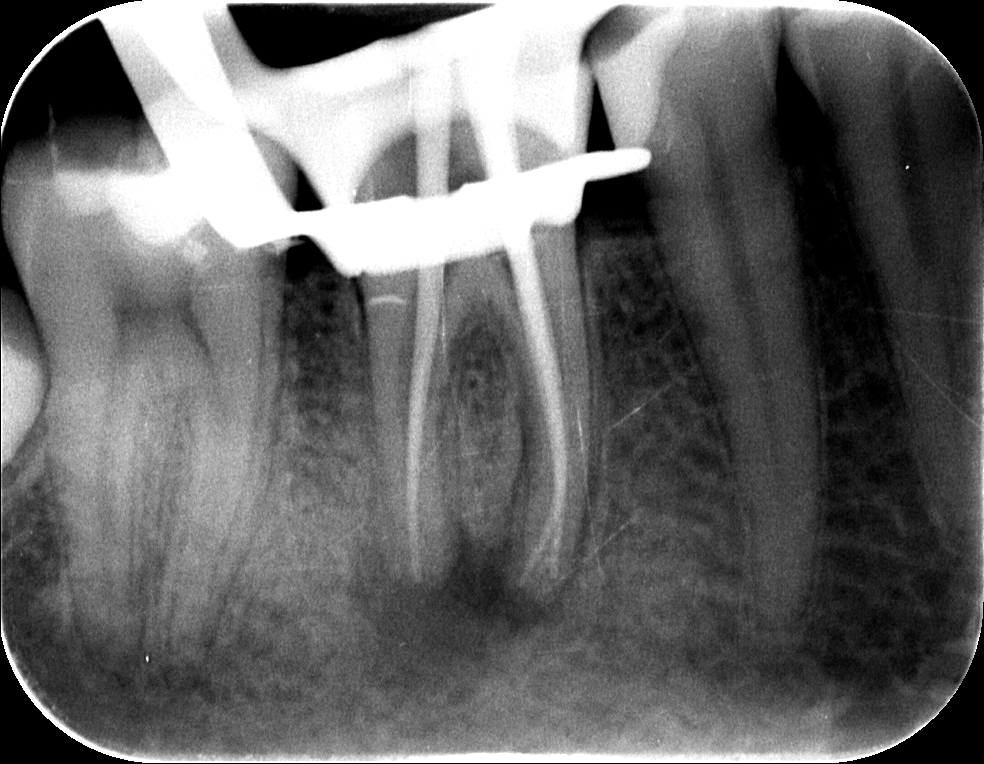

A régi gyökértömés eltávolítása, illetve a csatornák teljes feltárása után a későbbi gyökértömő „pálcikákkal” készült röntgenfelvétel. Ezen ellenőrizzük le a gyökértömés készítése előtt, hogy valóban jól dolgoztunk-e, és hogy sikerült-e minden csatornának eljutni a végéig.

mikroszkópos gyökérkezelés 2. kép